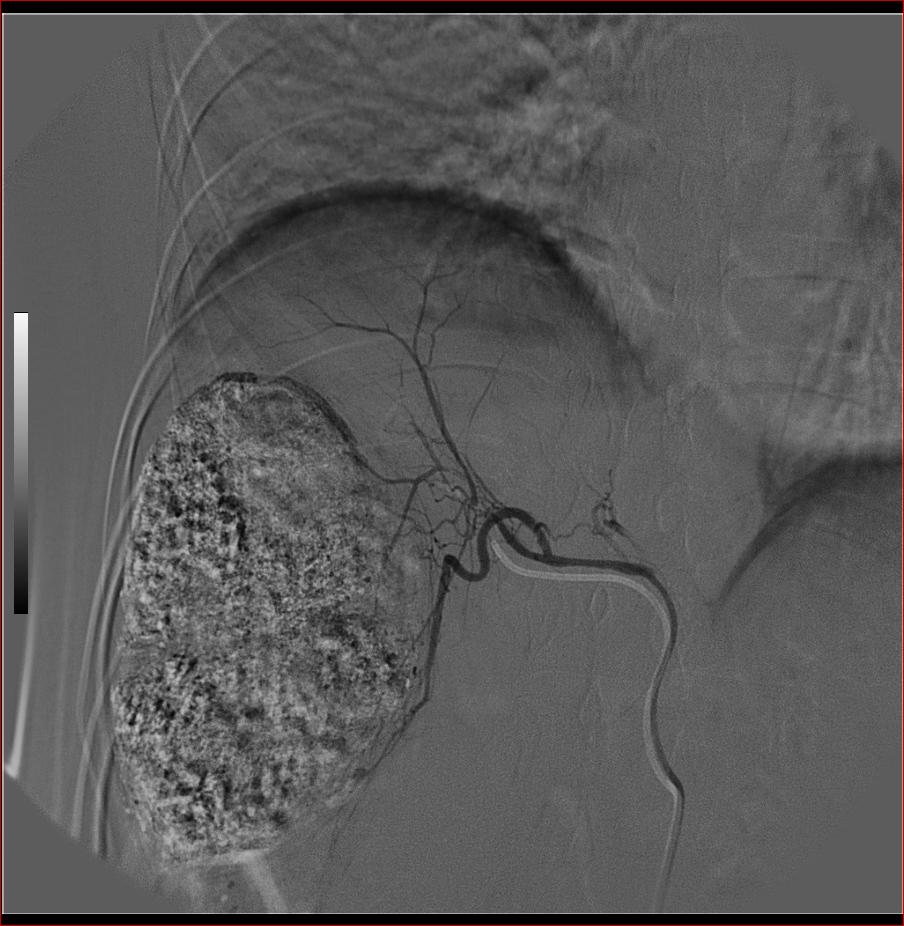

标题: DSA0138:F38Y,肝脏病变

第一次:

好牛的,右肝动脉发自肠系膜上动脉,不用微导管分次进行末梢栓塞,肿瘤染色完整。再次学习了。